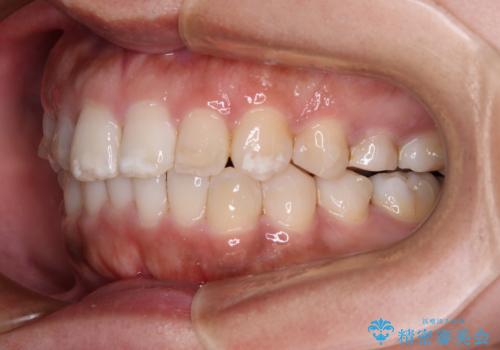

- 上下前歯の叢生を気にして来院された患者様です。

軽度な叢生であり、安価で短期間の治療を規模されていたため、インビザライン・モデレートを用いて矯正治療を行うこととしました。